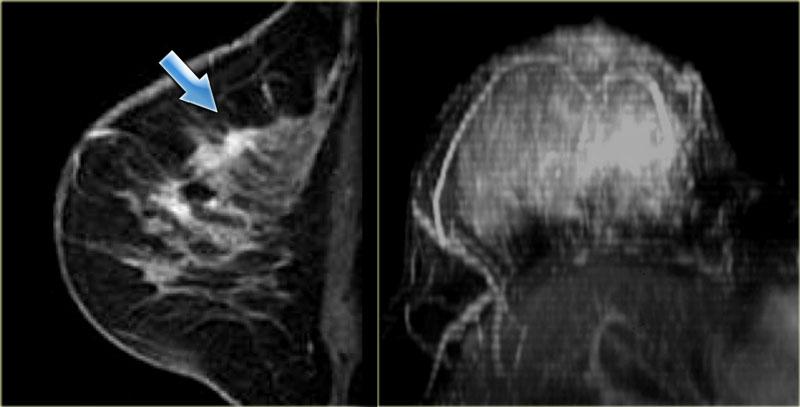

Hình ảnh ngoài cùng bên trái là ung thư tiểu thùy xâm lấn lan tỏa.

Bên phải là ảnh MIP cho thấy một vùng ngấm thuốc bất thường rộng lớn, được xác định là ung thư tiểu thùy xâm lấn lan tỏa.